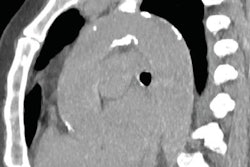

Preoperative assessment of aortic atherosclerotic burden with minimum radiation dose may be of value for patients undergoing cardiac or aortic surgery, said another group of Swiss researchers. They think ultralow-dose CT can optimize the surgical approach and decrease aortic plaques related to postoperative complications. Go to the CT Community, or click here.